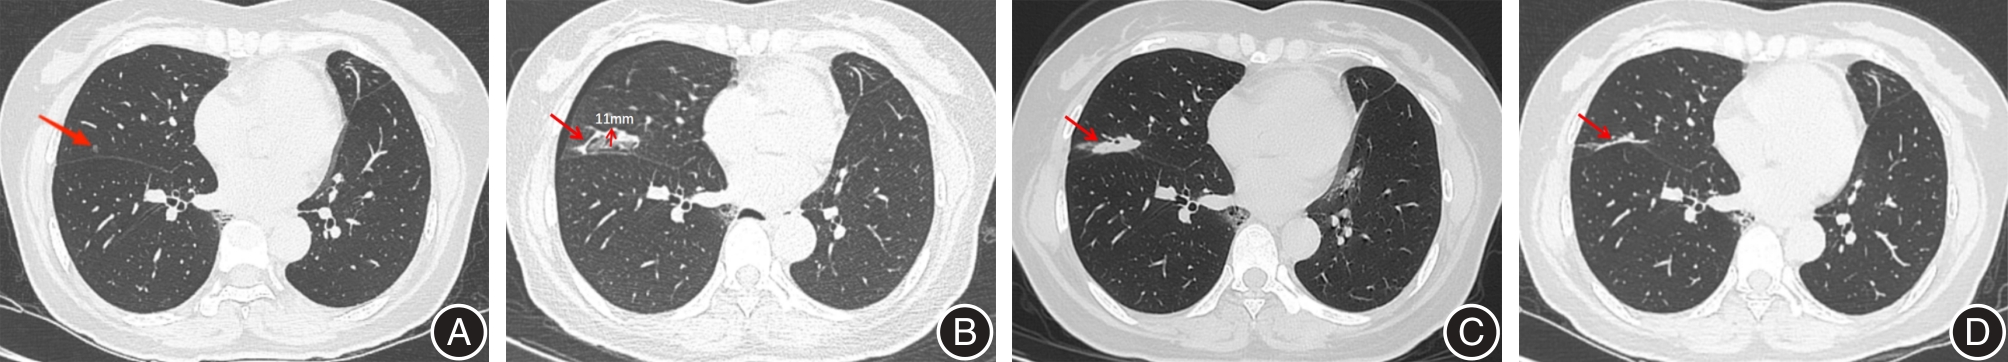

目的 旨在比较微波消融(MWA)和亚肺叶切除术治疗ⅠA期非小细胞肺癌(NSCLC)的临床疗效和并发症。 方法 回顾性收集2021年1月至2022年12月在云南省肿瘤医院治疗的ⅠA1-ⅠA3期NSCLC患者的资料。通过倾向评分匹配,共筛选出82例接受MWA的患者和 82例接受亚肺叶切除的患者。比较两组围手术期情况、近期疗效及并发症情况。监测评估无进展生存期(PFS)和无病生存期(DFS)。 结果 与亚肺叶切除组相比,MWA组手术时间短、术中失血量少、术后疼痛轻、住院时间短、住院费用低(P < 0.001)。所有患者均顺利完成手术,MWA组完全消融率为97.6%,局部控制率为87.8%。中位随访时间为26.5个月,两组之间的PFS和DFS差异无统计学意义(P > 0.05)。MWA组观察到的主要并发症为气胸(24.4%,20/82)和中度至重度疼痛(11.0%,9/82),而亚肺叶切除组则出现中度至重度疼痛(41.5%,34/82)和肺部感染(12.2%,10/82)。对MWA气胸发生的影响因素分析,单因素中6项变量与其相关,带入多因素logistic回归分析显示:肿瘤距胸膜最短距离(OR = 15.341, 95%CI: 1.699 ~ 24.367, P = 0.021)和穿刺胸膜次数(OR = 0.068, 95%CI: 0.001 ~ 0.612, P = 0.024)为气胸发生的独立危险因素。 结论 MWA治疗ⅠA期NSCLC患者疗效好、创伤小、费用低、恢复快,并发症少且轻;MWA和亚肺叶切除术有相当的PFS和DFS,是一种安全有效的治疗方法,值得在临床治疗中推广。

Objective This study aims to compare the clinical efficacy and complications associated with microwave ablation (MWA) and sublobectomyfor treating stage ⅠA non?small cell lung cancer (NSCLC). Methods Data from stage ⅠA1?ⅠA3 NSCLC patients treated at Yunnan Cancer Hospital between January 2021 and December 2022 were retrospectively collected. A total of 82 patients who underwent MWA and 82 patients who received sublobectomy were selected through propensity score matching. Periprocedural conditions, short?term efficacy, and complications were compared between the two groups. Progression?free survival (PFS) and Disease?free survival (DFS) were monitored and evaluated. The Kaplan?Meier method was employed to construct survival curves, and logistic regression was utilized to analyze the factors influencing complications. Results The MWA group exhibited shorter procedure times, less intraprocedural blood loss, less postprocedure pain, shorter hospitalization durations, and lower hospitalization costs compared to the sublobectomy group (P < 0.001). All patients successfully underwent the procedures, with a complete ablation rate of 97.6% and a local control rate of 87.8%in the MWA group. The median follow?up duration was 26.5 months. Survival curve analysis indicated no statistically significant differences in PFS and DFS between the two groups. The primary complications observed were pneumothorax (24.4%, 20/82) and moderate to severe pain (11.0%, 9/82) in the MWA group, while the sublobectomy group experienced moderate to severe pain (41.5%, 34/82) and pulmonary infection (12.2%, 10/82). Single?factor analysis demonstrated six variables influenced the occurrence of MWA pneumothorax. Multi?factor logistic regression revealed that the shortest distance from the tumor to the pleura (P = 0.021,OR = 15.341,95%CI: 1.699 ~ 24.367) and the number of punctures through the pleura (P = 0.024,OR = 0.068, 95%CI: 0.001 ~ 0.612) were identified as independent risk factors for pneumothorax. Conclusion MWA demonstrates good efficacy for treating stage ⅠA NSCLC due to minimal trauma, low cost, rapid recovery, few and mild complications. Additionally, MWA and sublobectomy exhibit comparable PFS and DFS, making MWA a safe and effective treatment method. Therefore, MWA is worthy of promotion in clinical practice.